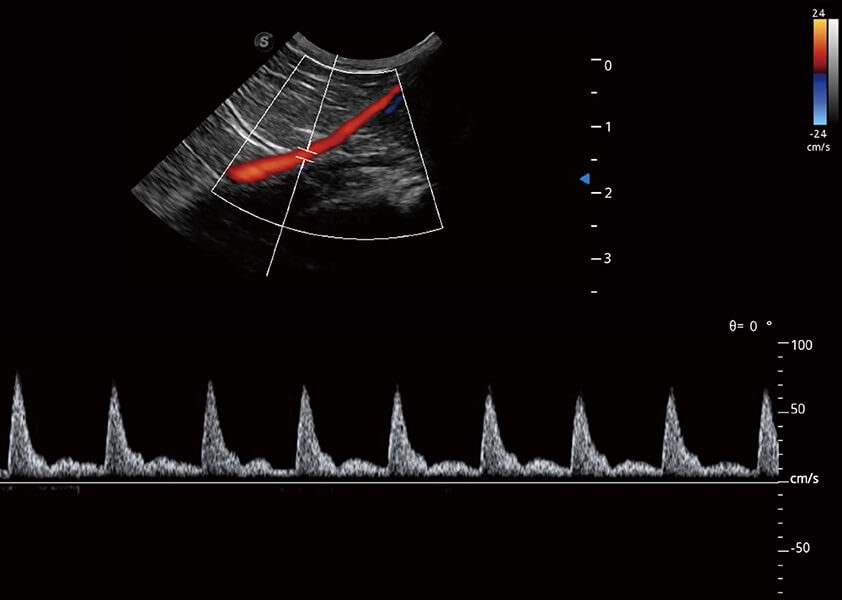

ProPet 60 作为一款高端台式动物超声设备,为动物医生的日常诊断提供了一系列贴合动物临床需求、解决临床实际问题的高级成像功能。凭借全系列高清探头,满足医生对腹部、心脏、生殖、浅表、肌骨等成像的所有需求,切实帮助您提升检查效率,提高诊断信心。

动物是人类最亲密的朋友和最值得信赖的伙伴。米兰官方网站也一直致力于探索动物专用的超声影像解决方案。 全新推出的ProPet系列,是米兰官方网站在动物超声影像智能化、专业化、精准化的一次跨越式革新。动物不能用言语来表述自己的不适,通过超声影像,ProPet系列搭建了动物医生与不同物种沟通的“桥梁”,为动物医生注入了“治愈之力”。